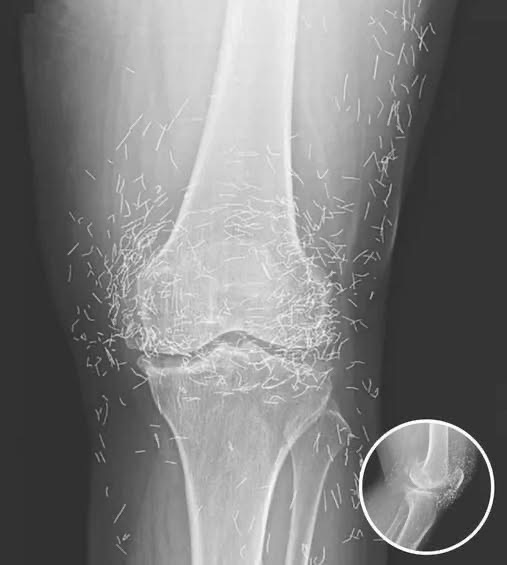

Doctors Stunned After Looking At This X-Ray Of Woman Suffering Joint Pain

A 65-year-old woman in South Korea experienced a shocking medical discovery when doctors found hundreds of tiny gold needles embedded in her knee tissue during a routine X-ray. She had been suffering from chronic osteoarthritis, a condition that causes joint pain, stiffness, and inflammation due to cartilage breakdown.

After conventional treatments such as painkillers and anti-inflammatory drugs failed to relieve her symptoms — and caused unpleasant side effects — she turned to acupuncture, a traditional therapy commonly practiced in many parts of Asia. Acupuncture involves inserting thin needles into the skin to stimulate specific points for pain relief or other health benefits.

In this case, the needles were intentionally left in her body as part of a long-term treatment strategy. Some practitioners believe that leaving gold needles or threads in place can provide ongoing stimulation to the affected area. However, medical professionals warn that this approach carries significant risks.

Dr. Ali Guermazi, a radiology expert from Boston University not involved in the case, explained that the human body can react negatively to foreign objects. Inflammatory responses, tissue damage, and infections are potential complications. Additionally, the embedded needles can interfere with medical imaging, making diagnosis more difficult.

One of the most serious risks comes with MRI scans. The powerful magnetic forces used in MRIs can cause metal objects to move within the body, possibly leading to punctured blood vessels or other life-threatening injuries. This makes metal implants a critical concern for patients who may need future imaging.

While acupuncture remains popular in many countries for managing joint pain, particularly in Asia, medical professionals caution that such alternative treatments should be thoroughly researched. The woman’s case, published in the New England Journal of Medicine, serves as a reminder that even traditional therapies can pose serious health risks when used in extreme or unconventional ways.